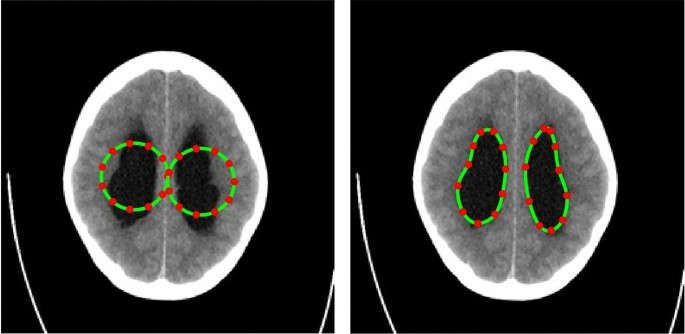

-

TC-1: In the first case, we consider a CT scan of the enlarged ventricles of a hydrocephalus patient. Figure 3 shows the segmentation results. The CT scan shows two enlarged ventricles. The left-hand side of Fig. 3 shows the contours initialized by the PICS user, and the right-hand side figure shows the optimized weights. By visual inspection, we can conclude that the results are satisfactory and PICS shows good performance when dealing with images that contain a single target object or when the number of target objects is known.